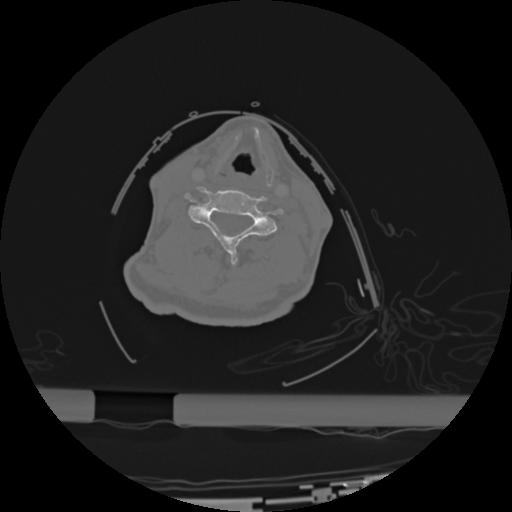

22 ANGIO,CE,Vol,0.5,ANGIO,,